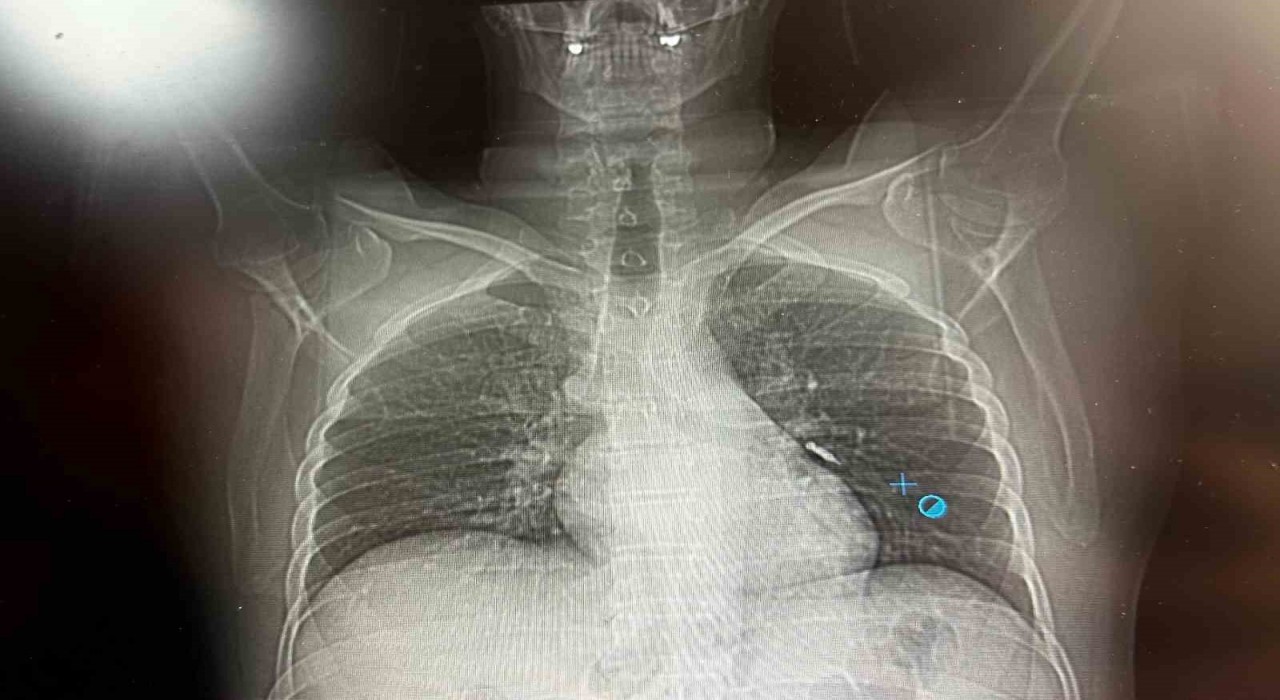

Göğüs Cerrahisi uzmanları Dr. Sadullah Aksoy ve Dr. Beniz İrem Ersoy Şığva tarafından hastaya bronkoskopi işlemi uygulandı. Sol akciğerin üst lobunda saplanmış şekilde tespit edilen vida, vidalı yapısı ve bulunduğu konum nedeniyle güçlükle yerinden oynatılabildi. Yapılan uzun ve titiz müdahale sonrası vida yerinden çıkarılamasa da hasta bir süre sonra geçirdiği öksürükle birlikte implant vidasını midesine gönderdi. Vida, daha sonra doğal yollarla vücuttan atıldı.

Konuya ilişkin konuşan Göğüs Cerrahi Op. Dr. Sadullah Aksoy, bir diş merkezinde diş tedavisi sırasında hastanın çenesine yerleştirilen implantın vida kısmının işlem esnasında yanlışlıkla aspire edildiğini belirtti. İlk olarak hastanenin ek hizmet binasında çekilen tomografi sonucunda, vidanın sol akciğerin hava yollarının yaklaşık dördüncü dalına kadar ilerlediği tespit edildiğini ifade eden Op. Dr. Aksoy, "Geçtiğimiz cumartesi günü öğle saatlerinde tarafımıza ulaşıldığında, hastanın Van Eğitim ve Araştırma Hastanesi’ne yönlendirilmesini istedik. Burada acil bronkoskopi planı yapılarak hasta kabul edildi. Hasta geldiğinde genel durumu iyiydi; solunumunu tamamen engelleyen bir bronş tıkanıklığı söz konusu değildi. Aynı gün hastamızı hazırladık. Bronkoskopi sırasında, implant vidasının sol üst lobun anterior segment bronşuna saplanmış pozisyonda olduğunu gördük. Üroloji bölümünde taş çıkarma işlemlerinde kullanılan cihazla müdahale ettik. İlk denemede implant tamamen çıkarılamadı ancak yerinden oynatılabildi. Bunun üzerine bir süre bekleyip hastayı yeniden bronkoskopi için hazırlamaya başladık. İşlem yaklaşık 3,5-4 saat sürdü ve saat 18.30 civarında hasta işlemden çıkarıldı" dedi.

Daha sonra hasta için yeniden bronkoskopi planladıklarını ancak bu süreçte hasta şiddetli bir öksürük geçirdiğini anlatan Aksoy, "Şiddetli öksürük sonrası yapılan kontrol akciğer filminde implant vidası görünmedi. Bunun üzerine toraks ve batın BT (bilgisayarlı tomografi) görüntülemesi istedik. Sonuçlarda implantın akciğerden çıktığı ve vücutta herhangi bir yerde bulunmadığı tespit edildi" diye konuştu.